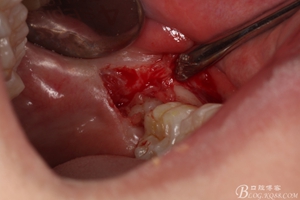

圖8. 翻瓣:建議翻小瓣

圖9.翻開瓣,可見38部分牙冠暴露